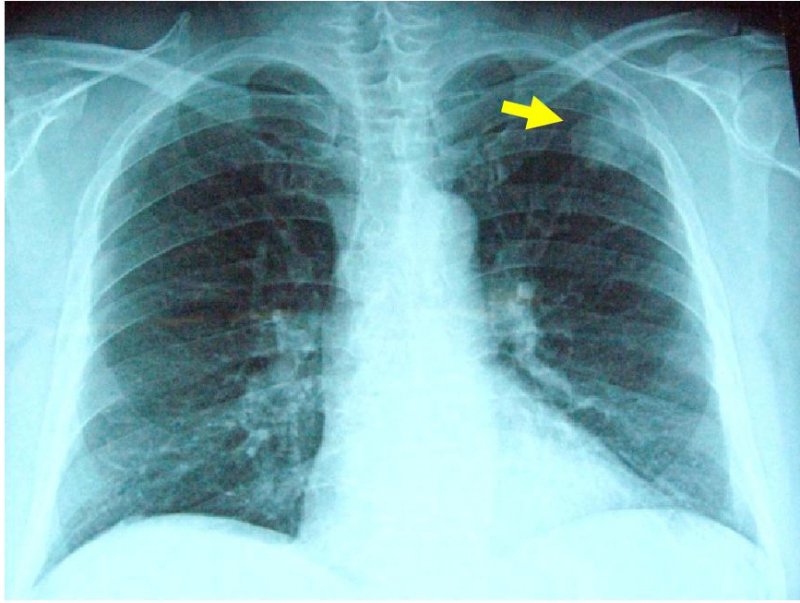

左肺癌の画像所見

胸部XP(左上肺野に腫瘤影あり)

胸部CT